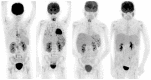

Background: Molecular nuclear medicine plays a pivotal role for diagnosis in a preclinical phase, in genetically susceptible patients, for radio-guided surgery, for disease relapse evaluation, and for therapy decision-making and follow-up. This is possible thanks to the development of new radiopharmaceuticals to target specific biomarkers of infection, inflammation and tumour immunology.

Methods: In this review, we describe the use of specific radiopharmaceuticals for infectious and inflammatory diseases with the aim of fast and accurate diagnosis and treatment follow-up. Furthermore, we focus on specific oncological indications with an emphasis on tumour immunology and visualizing the tumour environment.

Results: Molecular nuclear medicine imaging techniques get a foothold in the diagnosis of a variety of infectious and inflammatory diseases, such as bacterial and fungal infections, rheumatoid arthritis, and large vessel vasculitis, but also for treatment response in cancer immunotherapy.